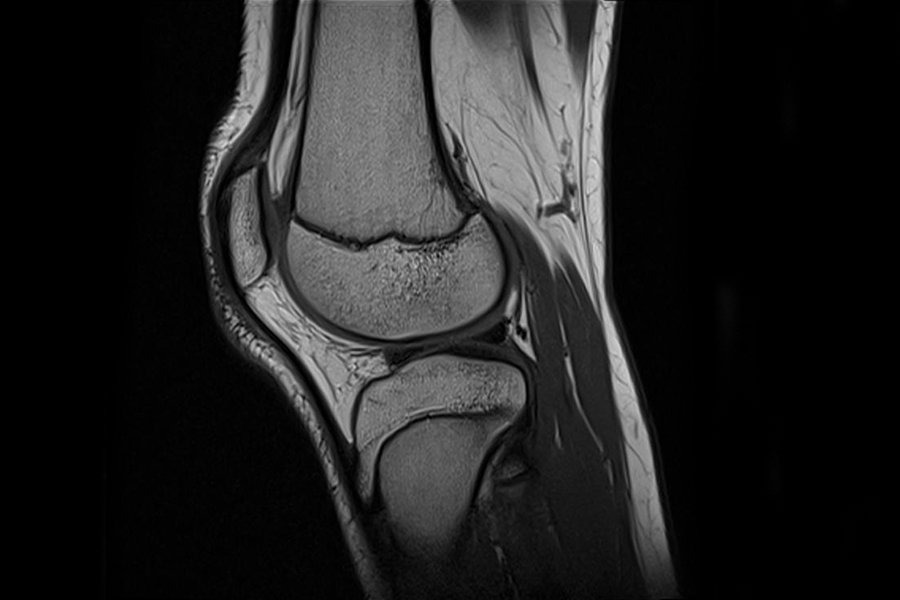

Die Magnetresonanztomographie (MRT) ist ein bildgebendes Verfahren, das mittels starker Magnetfelder und Radiowellen detaillierte Schnittbilder des Körpers erzeugt. Die Methode eignet sich besonders gut für die Untersuchung von Gehirn, Rückenmark und Wirbelsäule, inneren Bauch- und Beckenorganen, sowie von Muskeln und Gelenken. Abgesehen von der Darstellung der Anatomie lassen sich mithilfe der MRT auch funktionelle und dynamische Prozesse, wie etwa Stoffwechselvorgänge im Gehirn abbilden.

- Gelenke, Arme und Beine

Am Zentrum für Radiologie und Neuroradiologie stehen uns Kernspintomographen der neuesten Generation mit 3 Tesla und 1,5 Tesla Feldstärke zur Verfügung. Die Geräte ermöglichen hochauflösende MRT-Untersuchungen aller Körperregionen. Die detaillierten Bilder erlauben es uns, erkrankte Organe erkennen und beurteilen zu können. Gemeinsam mit den Fachabteilungen des Klinikums und den niedergelassenen Spezialisten entwickeln wir dann eine individuelle Therapie für unsere Patientinnen und Patienten.